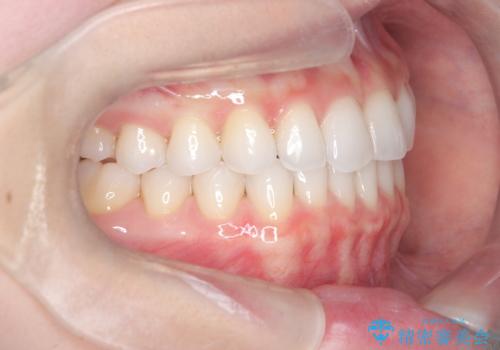

【インビザライン】前歯の凸凹をマウスピース矯正でなおしたい

- 前歯の凸凹を主訴に来院されました。

上の前歯は翼状捻転と呼ばれる状態でしたが、奥歯の遠心移動を行うことで配列スペースを確保することで綺麗に歯を並べることができました、

途中でインビザラインの使用時間が短くなってしまったため期間が予定より少し伸びましたが、1年半で満足いく結果となり患者様に喜んでいただけました。

下顎骨が右側に偏位していることにより下顎前歯の真ん中はずれています。